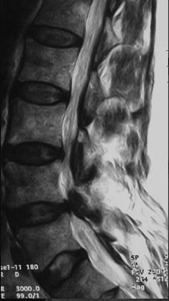

Aslında hastaların şikayetleri oldukça tipiktir. Bir süredir bel ağrıları olan, son 1-2 yılda giderek daha kısa mesafeler yol alınması tipiktir. Hastalar önce 500-600 metre yürürken giderek 200-300 metre, 50-60 metre yürüyebildiklerini, ağrı ve uyuşma nedeni ile 5-10 dakika dinlenemeden yola devam edemediklerini belirtirler.Hastanın kesin teşhisi bel omurgasının MR incelemesi ile konur. Bu tetkikte darlık teşhis edilir. Belde kayma veya laçkalık olup olmadığı teşhis edilir.